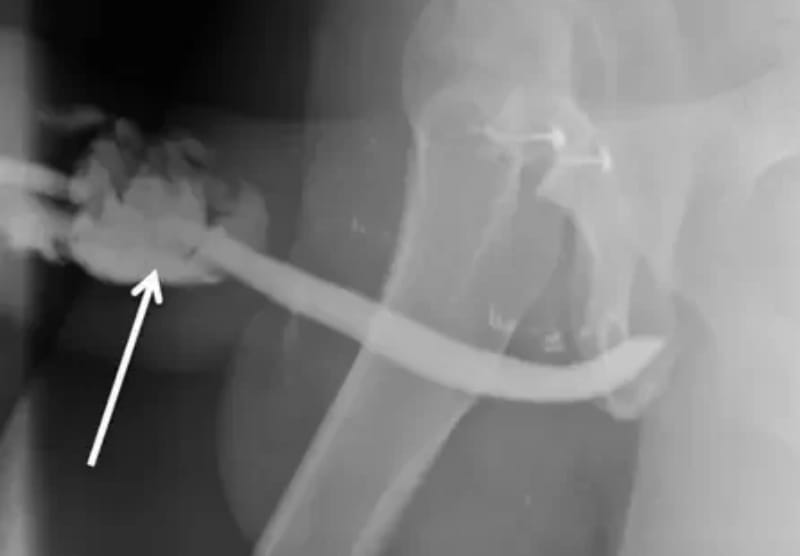

O tanzaniano teve de passar por uma cirurgia de emergência no hospital de Kilimanjaro para que o órgão fosse reconstruído, já que o órgão torcido e em um formato que os médicos descreveram como semelhante a um balão. Depois do procedimento e do período de recuperação, o pênis do paciente voltou a funcionar normalmente.